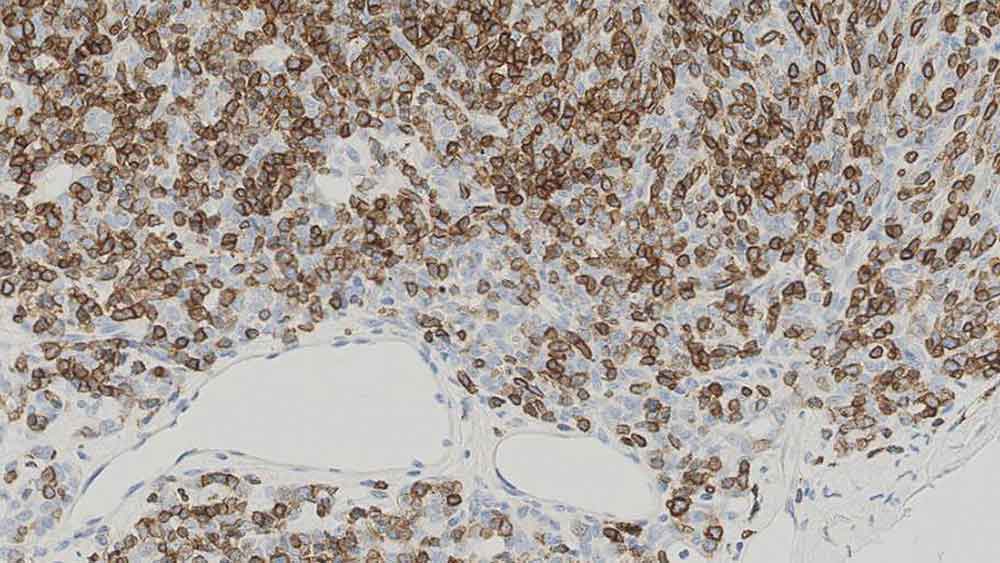

Human thymoma: immunohistochemical staining for CD1a. Note the neoplastic cells show a moderate to strong and distinct membrane staining reaction. CD1a: clone MTB1

Clone MTB1 detects cortical thymocytes, Langerhans cells in epidermis, interdigitating cells of dermis and interdigitating cells of stratified squamous epithelium of tonsil. Clone MTB1 may also detect small focal groups of lymphocytes outside the germinal centers of tonsil indicating a cross-reaction with CD1b antigen.